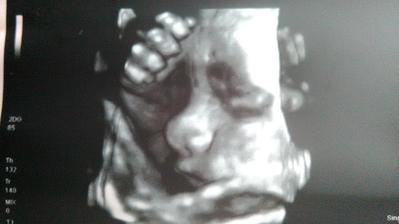

Bude to Pinocchio 🙂

=oD jj, zrovna měl ruku u pusinky a vypadá jako Pinocchio chudáček